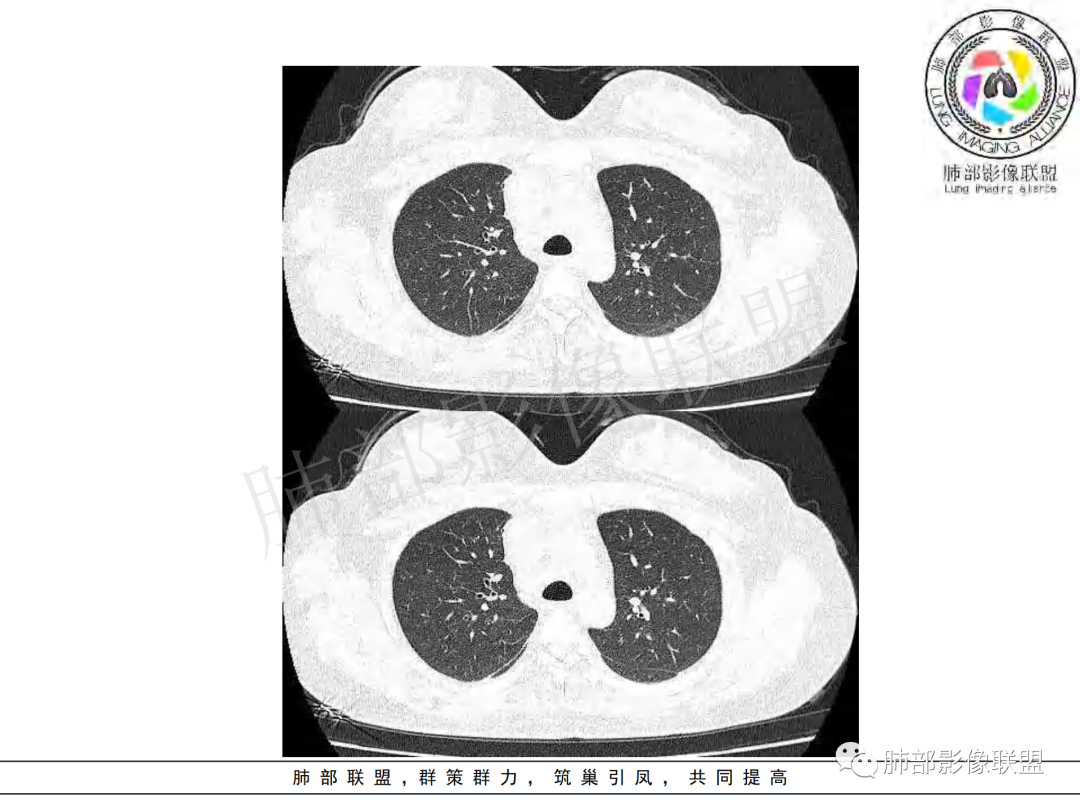

纵隔多组及右侧肺门多发肿大淋巴结,部分融合,不均匀强化,内见斑片状坏死区及环状强化,后者坏死边界尚清晰,肺门区肿大淋巴结与肺组织边界不清,年轻女性,8个月病史,发热首发症状,考虑淋巴结核并向肺内侵及(破溃?),鉴别淋巴瘤

女,20,病程长达8月,发热、胸痛、右侧胸腔积液病史。胸部CT:右肺门旁不规则肿块影,右中间支气管腔内结节,纵隔多发淋巴结肿大;强化不均匀,灶性坏死灶,环形强化;右侧少量胸腔积液并局部肉芽肿样突起。年轻女性,长病程,多部位,考虑慢性炎症,结核?鉴别肿瘤。

年轻女性,慢性病程,发热、胸痛。右肺门旁不规则肿块影,纵隔多发淋巴结肿大;强化不均匀,环形强化;右侧少量胸腔积液;首先考虑结核,鉴别肿瘤,结节病。

年龄和病史比较符合结核,但是中叶支气管好像堵塞了,管腔有新生物,恶性肿瘤也不能排除,做一个支气管镜应该能确诊

年轻女性,右肺门区病变伴纵隔淋巴结肿大,强化显示环形强化,考虑结核可能性大

年轻女性,右侧肺门一肿块,边缘不规则,纵膈淋巴结肿大,环形强化,右侧胸膜少量积液,发热首先考虑结核鉴别恶性淋巴瘤

支气管腔内有占位,肺门区病灶和胸膜结节明显强化,淋巴结环状强化为主,部分明显强化,年轻女性,首先考虑结核,鉴别腺癌

青年女性,发热、胸痛、右侧胸腔积液病史,病程8个月。曾多次抗炎后均有好转。CT:右肺门旁肿块影,双侧胸膜结节,纵隔多发淋巴结肿大,边缘模糊;增强渐进性明显强化,纵膈淋巴结较彻底坏死灶,边缘环形强化。考虑结核,鉴别恶性肿瘤。

女性,20岁。高热、畏寒。右肺上叶近肺门区不规则肿块,周围斑点、片小结节影伴肿大淋巴结,肿块包绕并突入右主支气管腔内,增强后肿块不均匀强化,淋巴结环形强化中心低密度,考虑结核。

本例患者,年轻女性,慢性病程,多次抗感染治疗效果不佳,实验室检查示白细胞及中性粒细胞不高,不支持普通细菌感染,虽然肺泡灌洗液X-Pert检测阴性,结合患者胸部CT结核感染亦不能排除,胸部CT主要表现为右侧肺门及纵隔淋巴结肿大,仔细观察不难发现右中间支气管内新生物凸向管腔内,增强扫描,右肺门(10R)及纵隔淋巴结(2R,4R)明显不均匀强化,内部呈不规则低密度无强化区,被周边高强化区包绕(环形强化)的特点,首先应当想到纵隔淋巴结结核诊断。淋巴结分布亦不符合肺部恶性肿瘤迁徙途径。